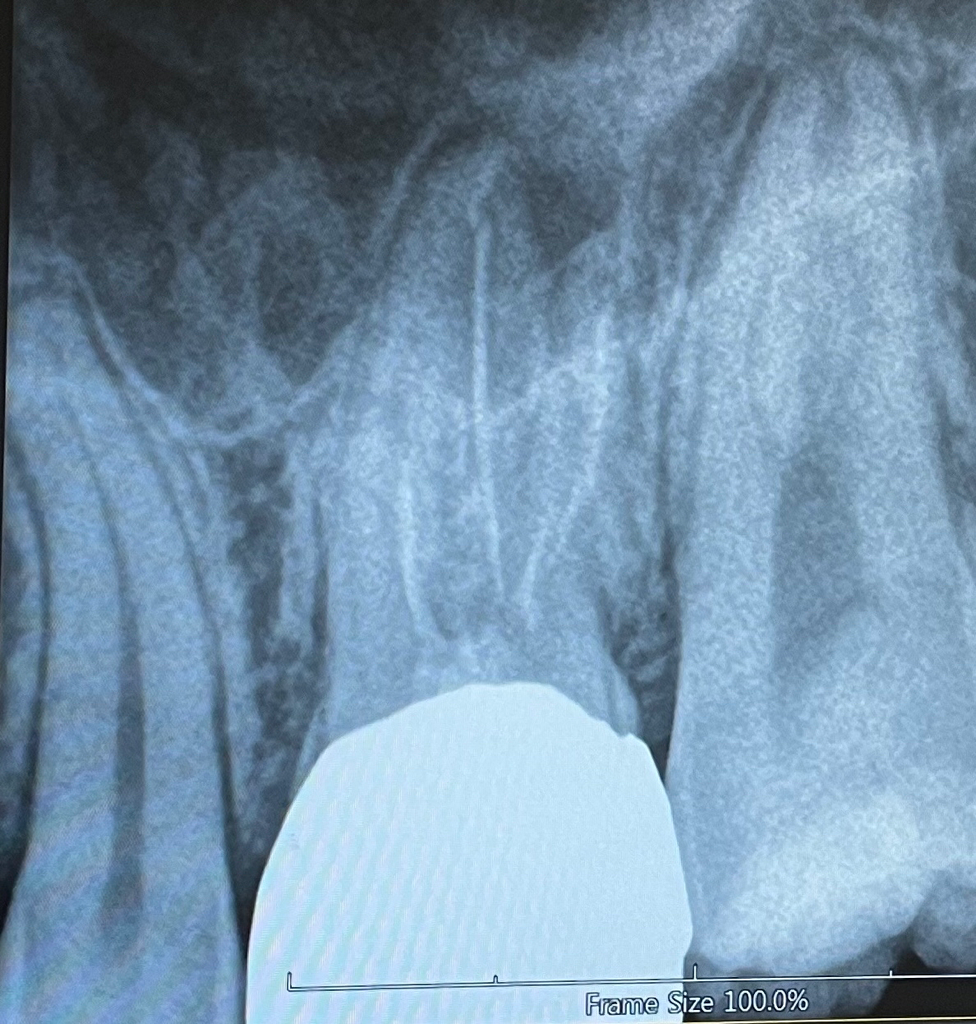

크라운 씌운곳이 아픈데 신경에 문제가 있는건가요?

크라운 씌운곳이 씹을때마다 너무 아프고, 누를때는 진통이 심합니다. 그래서 그 다음날 바로 내원해서 사진을 찍었습니다. 신경에 문제가 있나요? 크라운을 벗기고 다시 신경치료를 받아야하나요?

사진을 봤을때는 치근단부위에 병소가 있는것으로 보입니다.

치근단부위에 병소는 근관내 감염이 일어났을 경우에 생기는 데 재신경치료를 해서 치료를 할수 있어요.

사진이 흐려서 정확한 진단을 하기는 힘들지만

통증이 지속된다면 크라운을 제거 후 다시 신경치료 하셔야합니다.